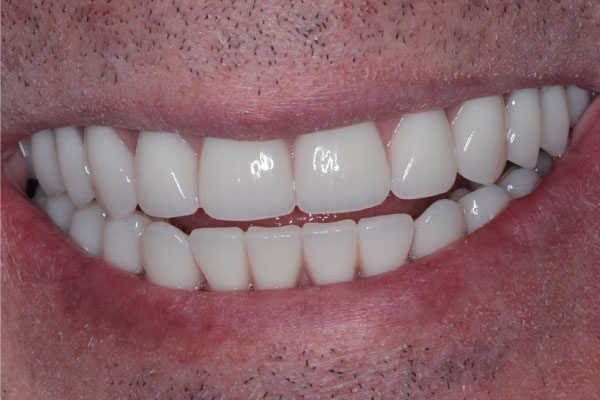

Имплантация зубов: фото «До» и «После»

Фото ДО

Фото ПОСЛЕ

All-on-4